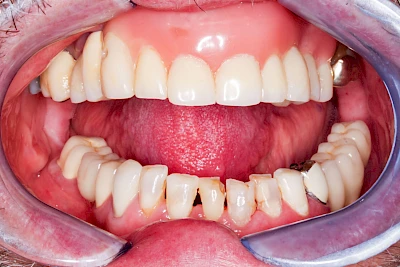

Heute werden in Deutschland Menschen mit Lippen-Kiefer-Gaumenspalten bereits ab Geburt von Experten verschiedener Fachrichtungen (Mund-Kiefer-Gesichtschirurgen, Kieferorthopäden, Logopäden) betreut, damit entsprechende Korrekturen schon frühzeitig erfolgen können. Gerade jedoch bei älteren Menschen ist dies nicht immer geschehen. Diese Menschen tragen häufig technisch aufwendige Zahnprothesen.